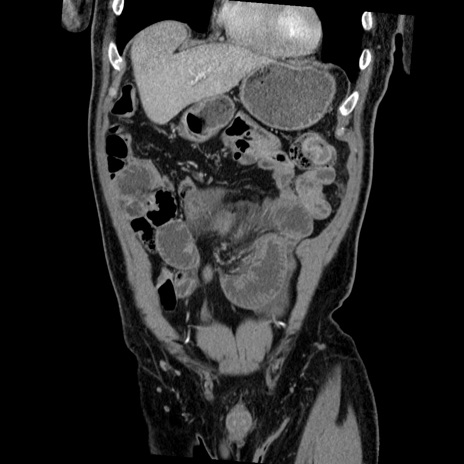

症例22(冠状断像)

【症例】50歳代男性

【主訴】腹痛

【現病歴】AVMからの被殻出血のため回復期リハ病棟入院中。 本日午後3時頃急に下腹部痛が出現した。

【既往歴】AVM、被殻出血、虫垂炎、高血圧

【身体所見】意識晴明、左半身不全麻痺、会話の理解は良好、36.5°C、腹部:膨隆、全体に板状硬、下腹部正中に圧痛点あり、反跳痛-、筋性防御不明、右下腹部にope scar

【データ】WBC 9400、CRP 0.06